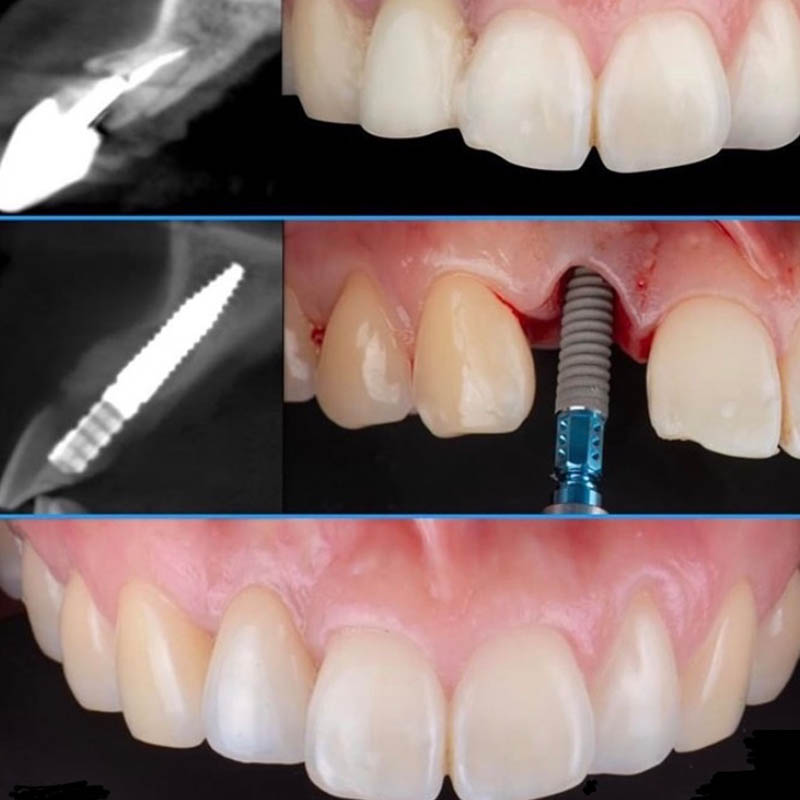

На современном этапе достичь нужного результата стоматологического лечения нередко удается только путем дентальной имплантации. Специалисты клиники Совершенная улыбка тоже активно используют данную методику. При этом в своей деятельности они располагают всеми предпосылками для проведения как быстрой имплантации, когда все действия врач завершает в течение одного посещения, так и операции по классической методике, которой предшествует целый ряд подготовительных процедур, костная пластика.

Успех имплантации в клинике обеспечивается не только мастерством специалистов, высоким уровнем диагностических мероприятий, но использованием качественных материалов, отлично зарекомендовавших себя в сложных клинических случаях или при недостаточной плотности костной ткани. В совокупности такие предпосылки позволяют сократить противопоказания к проведению операции, получить отличные отдаленные результаты. При этом, стремясь обеспечить каждого пациента самым эффективным результатом ортопедического лечения, что гарантирует имплантация, наши специалисты имеют возможность проводить ее моделями разных ценовых категорий. Столь привлекательные финансовые условия позволяют воспользоваться данной методикой людям с любым уровнем доходов.

Примеры работ